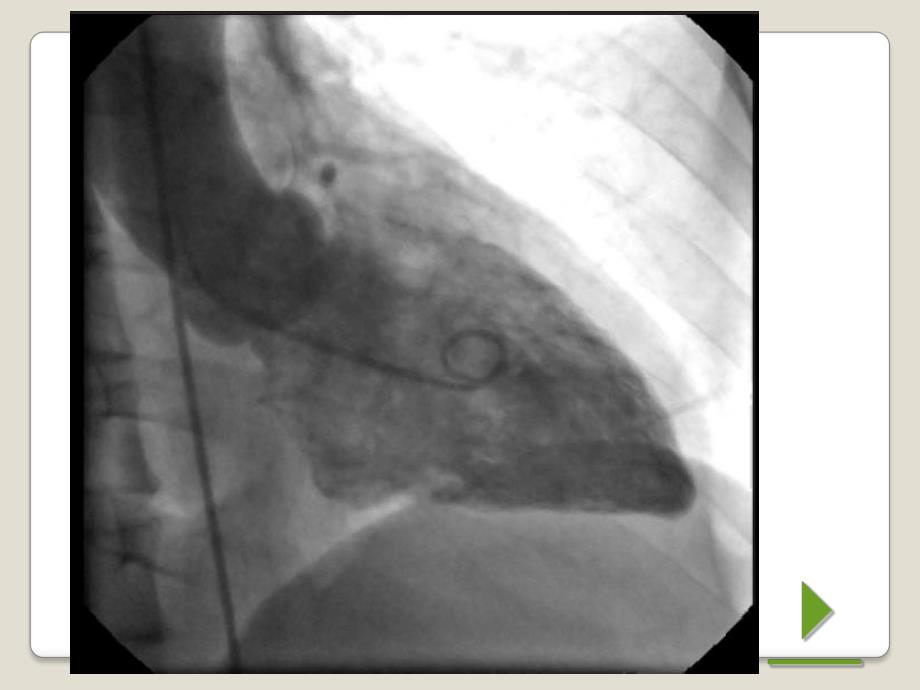

4、个过程中保持体位和投射方向在整个过程中保持不变。不变。心电图触发心电图触发X X线脉冲线脉冲与固定频率与固定频率工作方式不同,工作方式不同,X X线脉冲与心脏的搏线脉冲与心脏的搏动节律相匹配,以保证系列中所有的动节律相匹配,以保证系列中所有的图像与心律同相位,并可控制曝光的图像与心律同相位,并可控制曝光的时间点在血管运动最小的时刻。时间点在血管运动最小的时刻。此方式主要用于心脏大血管的此方式主要用于心脏大血管的DSADSA检查。检查。能量减影能量减影也称双能减影、也称双能减影、K-K-缘减影,是利用缘减影,是利用对比对比剂与周围组织间能量衰减的差别进行减影。即进行剂与周围组织间能量衰减的差别进

10、触发心电图触发X X线脉冲线脉冲与固定频率工与固定频率工作方式不同,作方式不同,X X线脉冲与心脏的搏动线脉冲与心脏的搏动节律相匹配,以保证系列中所有的图节律相匹配,以保证系列中所有的图像与心律同相位,并可控制曝光的时像与心律同相位,并可控制曝光的时间点在血管运动最小的时刻。间点在血管运动最小的时刻。此方式主要用于心脏大血管的此方式主要用于心脏大血管的DSADSA检查。检查。后处理功能是后处理功能是DSADSA有别于常规血有别于常规血管造影的特征之一,也是计算机辅管造影的特征之一,也是计算机辅助的数字成像技术(助的数字成像技术(CTCT、MRMR等)均等)均具有的功能。具有的功能。DSA DS